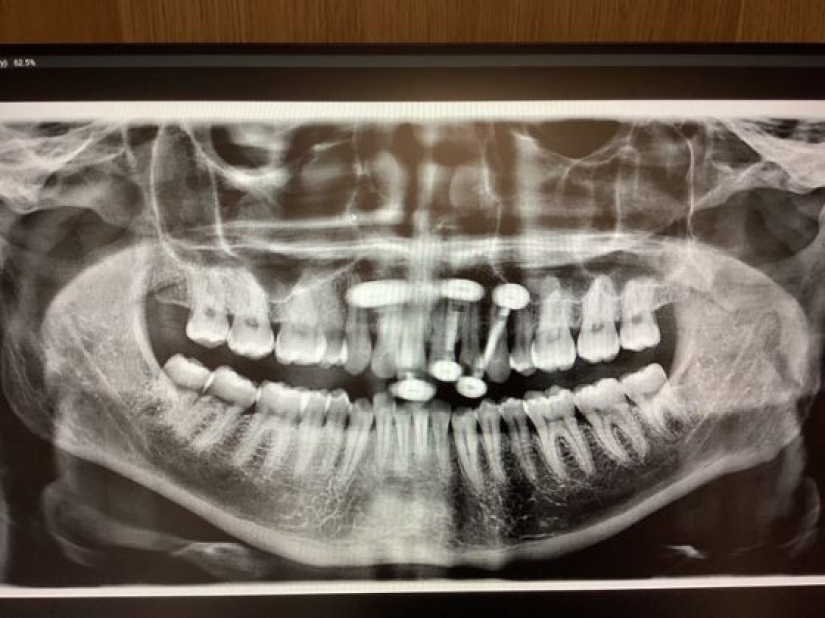

11. “At the moment the tooth fairy owes me a lot of money. I am 33 years old and here are my x-rays showing my remaining baby teeth.”